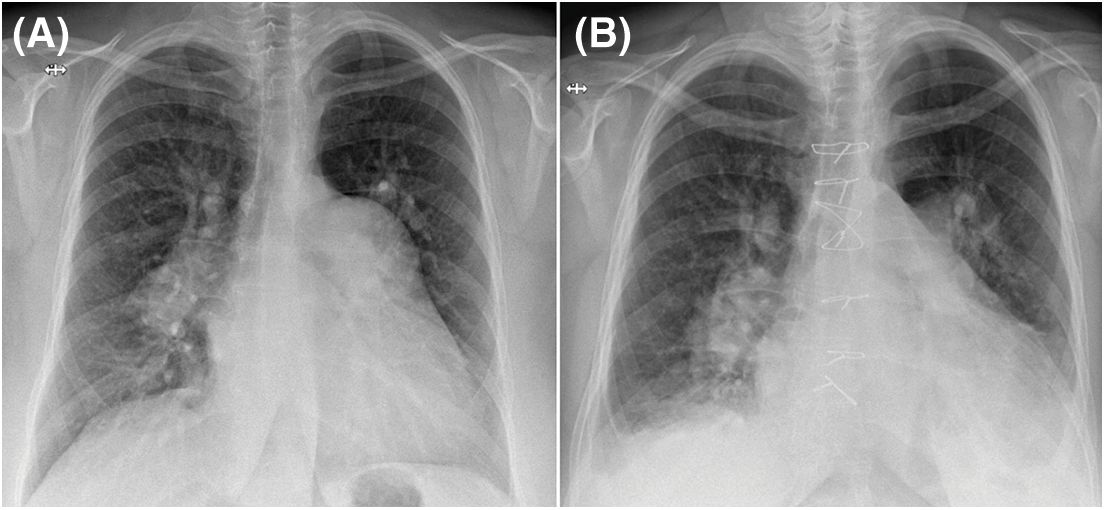

Figure 3: Chest X-ray PA view (A) PAA is conspicuous on the preoperative exam. (B) The PAA is not visible anymore postoperatively

The ASD was closed with a unidirectional valved patch; a reductive pulmonary arterioplasty treated the PAA and LMCS. The valved patch (with a 7 mm fenestration) was constructed before cardiopulmonary bypass (CPB) from a 5 × 8 cm rectangular piece of fresh pericardium using a previously described technique [4]. Two semi-circular segments were resected from either side of the PAA incision, aiming for a 30 mm reconstructed PA. CPB was weaned-off under mild doses of dobutamine and inhaled nitric oxide. CPB and aortic cross-clamping times were 103 and 89 min, respectively. The patient’s postoperative course was uneventful (no PAH crisis occurred). The patient was extubated six hours after the procedure and discharged on the eighth postoperative day (Fig. 3B).

PAH-specific dual therapy was continued postoperatively. After three months, exercise tolerance significantly improved, there was no residual shunt, reverse remodeling of the right ventricle had occurred (Fig. 4), PA diameter was 33 mm. An invasive reassessment found PAPs = 54 mmHg, PAPm = 35 mmHg, PVR = 3.3 WU, and a non-significant LM residual stenosis (30%) (Fig. 1B).